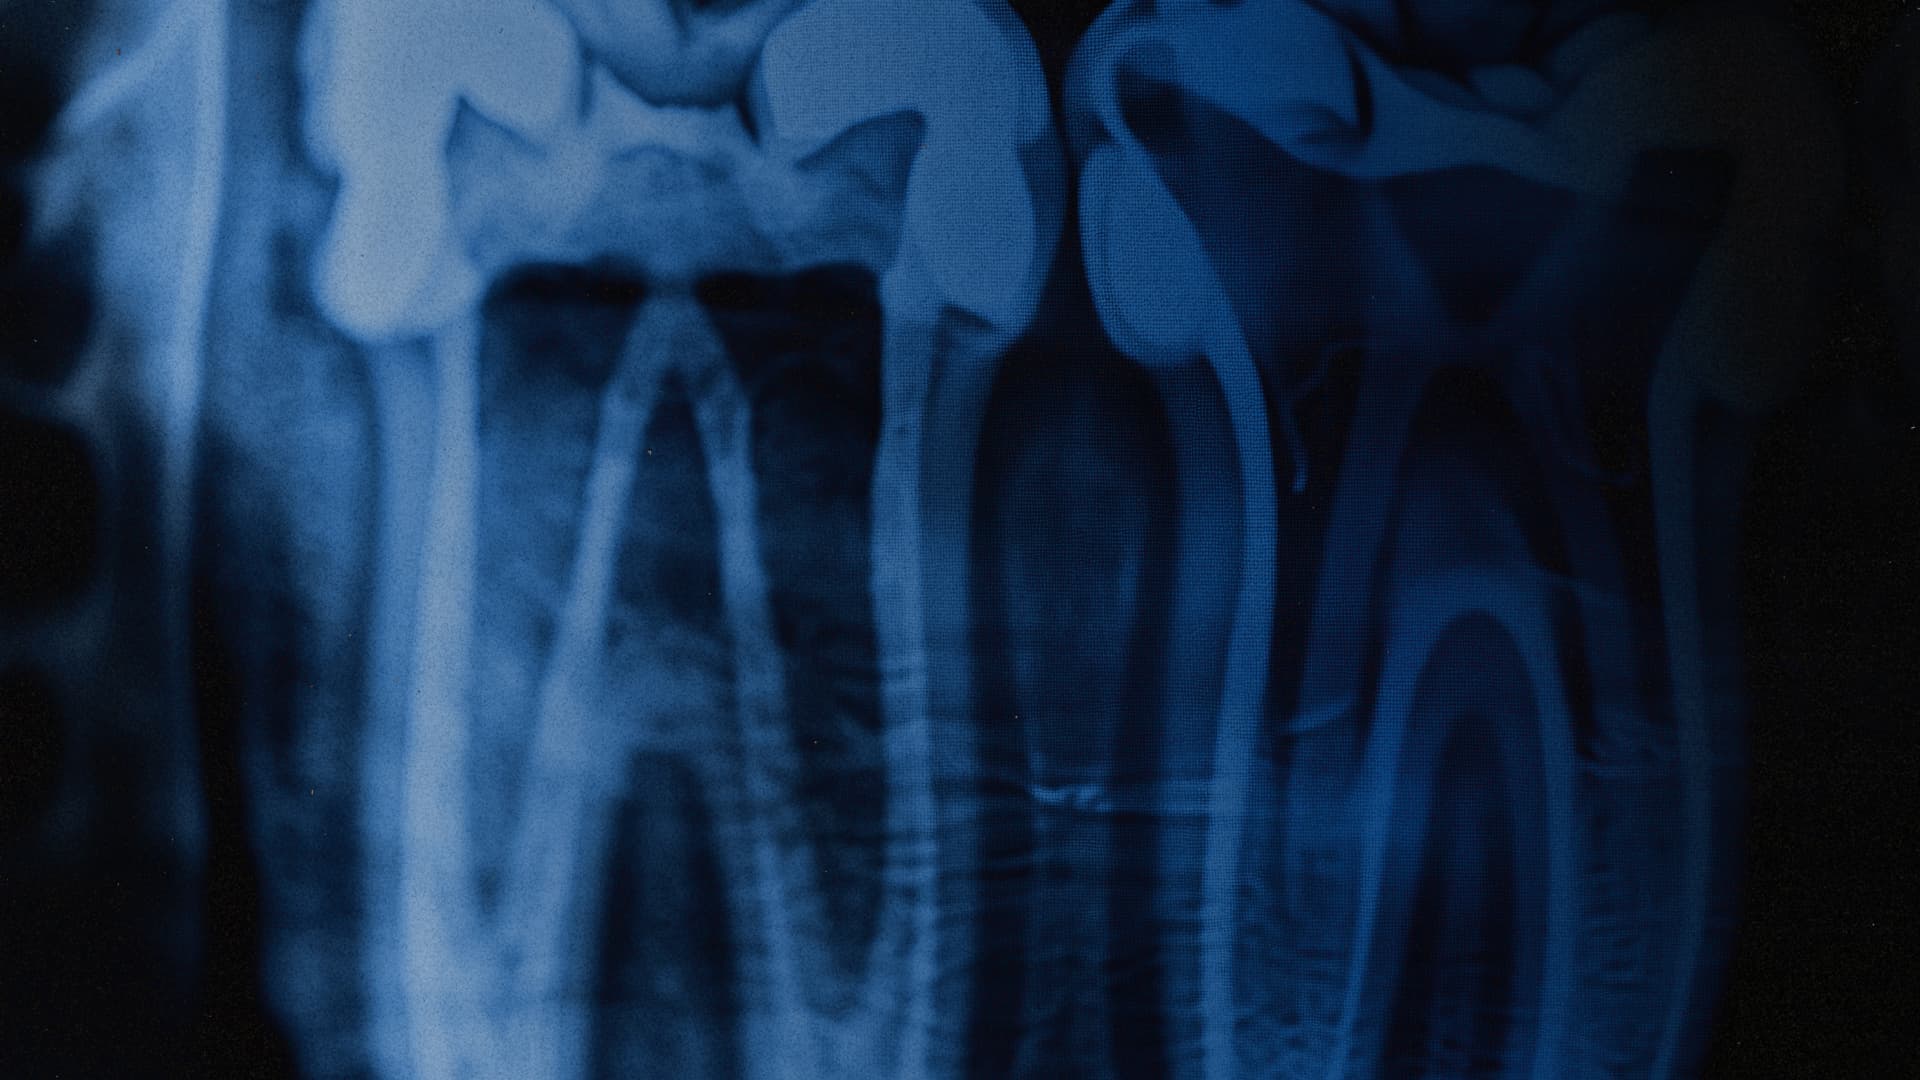

- Медичний компонент.

Протезування, імплантація, реконструкція зубних рядів, відновлення функції жування та структури обличчя. Це повертає не лише фізичний комфорт, а й базову впевненість у собі. - Психологічний супровід.